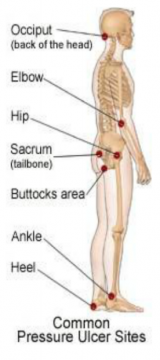

| 09:50, 23 במאי 2013 | פצעעקב5.png (קובץ) |  |

| 09:45, 23 במאי 2013 | פצעעקב4.png (קובץ) |  |

| 09:37, 23 במאי 2013 | פצעעקב3.png (קובץ) |  |

| 09:31, 23 במאי 2013 | פצעעקב2.png (קובץ) |  |

| 08:48, 23 במאי 2013 | משטחלחץ2.png (קובץ) |  |

| 08:09, 23 במאי 2013 | משטחלחץ1.png (קובץ) |  |

| 08:06, 23 במאי 2013 | מיפוילחצים1.png (קובץ) |  |

| 08:01, 23 במאי 2013 | שינויתנוחה1.png (קובץ) |  |